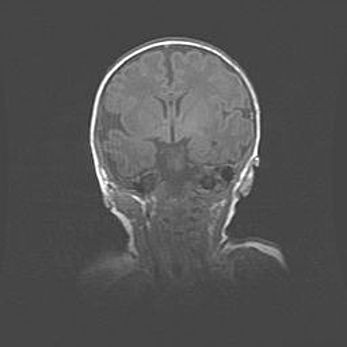

Подострая гематома правой гемисферы мозжечка.

Наружная гидроцефалия.

Возраст: 15 дней

Вес: 3100 г

Пол: женский

Окружность головы: 37 см

Срок гестации: 35-36 недель

При открытой наружной форме гидроцефалии у новорожденных расширяются и переполняются субарахноидные пространства.

Кровоизлияния в мозжечок имеют две клинико-анатомические формы: полушарные гематомы и кровоизлияния в червь.

К появлению этой патологии может привести: повреждения головного мозга, возникающие в результате асфиксии и гипоксии плода при беременности, или травмы во время родов. Редко гематома мозжечка может быть результатом первичной коагулопатии и сосудистой мальформации, диссеминированном внутрисосудистом свертывании, изоиммунной тромбоцитопении.